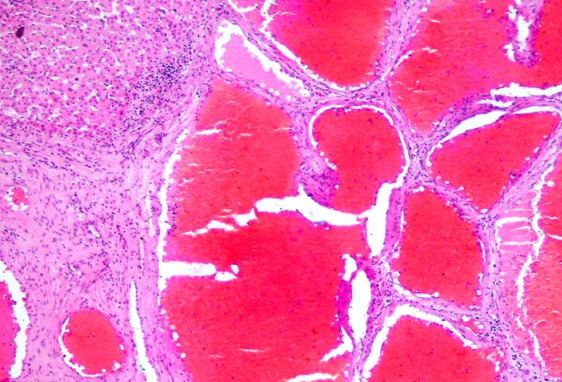

Stomatoloog leidis 23 a mehe suu läbivaatusel kurgunibu piirkonnast kasvaja (vt pilt ülal). Kasvaja ei põhjustanud muid kaebusi kui vähest neelamishäiret. See eemaldati ja saadeti patohistoloogiliseks uuringuks. Milline järgnevatest fotodest sobib antud diagnooisga?

65 a mehel oli 3 kuu jooksul huulele tekkinud haavanduv moodustis (vt pilt ülal). See eemaldati kirurgiliselt ja saadeti patoanatoomia laborisse uuringuks. Milline toodud fotodest sobib selle kliinilise diagnoosiga?